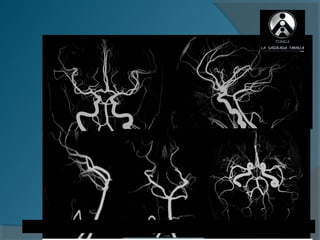

Angiografía por RM

ANGIORM 3.0T

   AUMENTO

DE RESOLUCIÓN

   VISUALIZACIÓN

DE VASOS

PERIFÉRICOS|

ANGIORM VASOS DE CUELLO

2D   3D